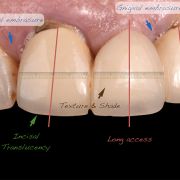

TV Show presenter visited my clinic complaining of unpleasant bridge that had been placed couple of years ago. Thorough clinical and radiographic examination was done including smile, teeth and gingival analysis. Implant as a treatment option was excluded due to patient preference. Let us see how I dealt with this case!